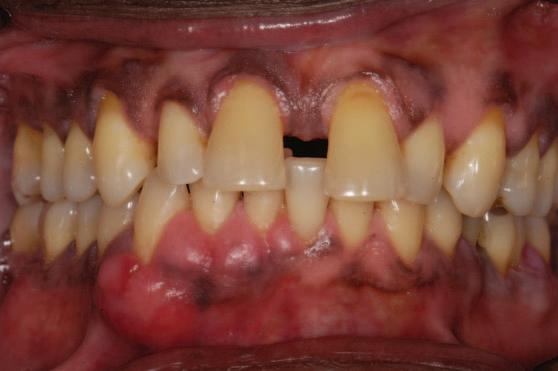

A 30-year-old patient presented to your clinic complaining of a discoloured front tooth (Figures 1 and 2). There was no pain or other symptoms associated with it and it has become increasingly discoloured over time.

1. What is the likely reason for this type of discolouration?

2. What special tests do you perform as part of your exam?

3. What are the potential sequalae for this tooth?

4. What are the possible treatment options for

this tooth and what are the potential difficulties with doing a root canal treatment?

Answers on page 45.

FIGURE 1: Patient presenting with discoloured front tooth. FIGURE 2: Periapical radiograph 1.